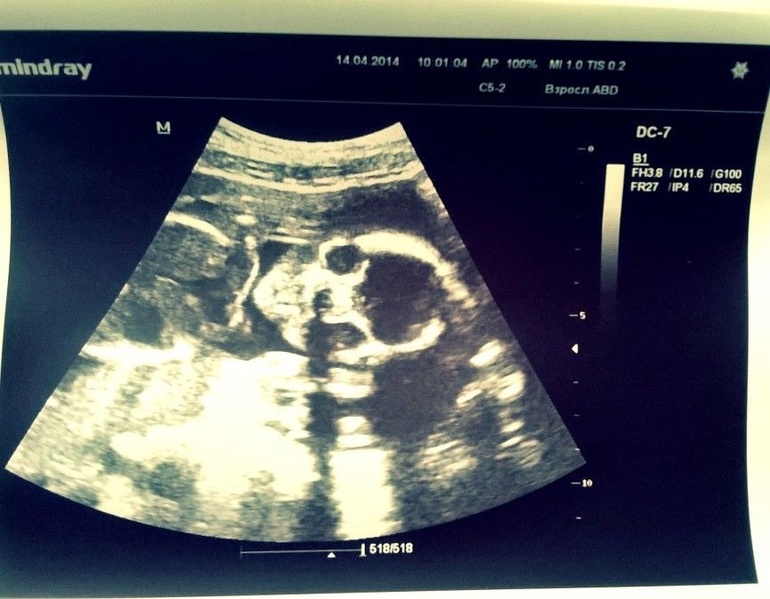

Единственное, что не понравилось врачу, которая делала узи, так это низкий гемоглобин 114 (при норме 145)... Сказала, что это к маловодию... Что делать с этим решу 16 числа с врачом...Малыш показывал себя во всей красе... Начиная от личика

Заканчивая пяточкой (хотя по мне так больше на ручку похоже

)